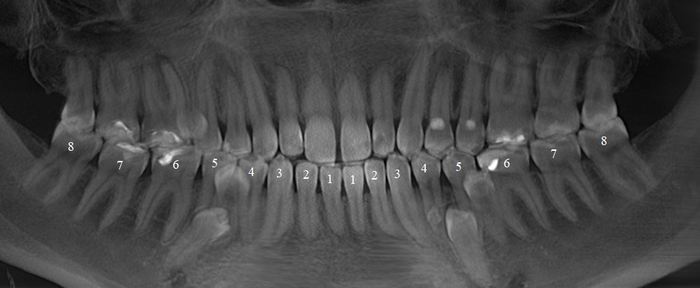

Согласитесь, не особо эстетично. Ортопантомограмма:

Контрольная ортопантомограмма:

Прицельный снимок:

Я согласен, что эстетика хромает. Давно пора менять временную коронку на постоянную, что улучшит результат. Но, как я говорил, все упирается в финансы.